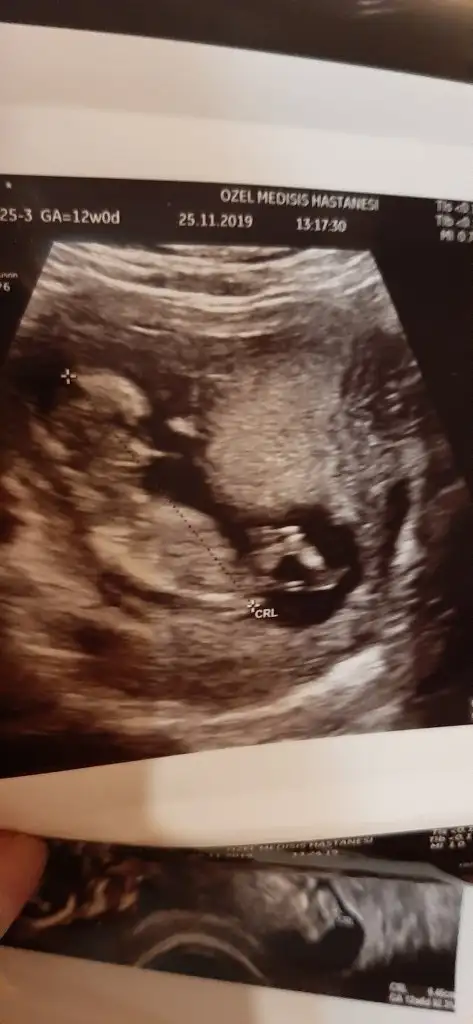

ERKEKMİ CANM... NUB İÇİN BU AÇIDAN BAKILMIYO CANISIKizlar nub teorisi bu açidan da ise yariyor mu bilen varsa yorum yaparsa sevinirim insan meraklaniyor işte❣

Yok canim doktor kesin biseysoyleyemiyorum dediERKEKMİ CANM... NUB İÇİN BU AÇIDAN BAKILMIYO CANISI

TESTİSLER KIZLARDAKİ DUDAKLARA DA BENZİYO OLABİLİR OYUZDEN NET DEMEMİŞTİR...YANDAN ÇEKİLMİŞ USG YOKMU YATARKEN FALANYok canim doktor kesin biseysoyleyemiyorum dedi

var canim ama burda hic belli degilTESTİSLER KIZLARDAKİ DUDAKLARA DA BENZİYO OLABİLİR OYUZDEN NET DEMEMİŞTİR...YANDAN ÇEKİLMİŞ USG YOKMU YATARKEN FALAN

BEN ERKEK DİYORUM =)var canim ama burda hic belli degil

ögrenince paylasiyim sizinle

MERAKLA BEKLİYORUM NE ZAMAN BİDAKİ KONTROL

10 gun sonra tekrar bakabiliriz dedi bizim 10 gun sonra gidince dogum paketindeki kontrollerimizden dusmedigi icin.oyle dediMERAKLA BEKLİYORUM NE ZAMAN BİDAKİ KONTROL